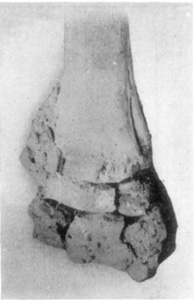

Simple Fracture is a condition where the continuity of the bone has been broken without serious destruction of the soft structures adjacent, and where no opening has been made to the surface of the flesh. Such fractures do not reduce the bone to fragments. Long bones are frequently subjected to simple fracture, while short thick bones, such as the second phalanx, may suffer multiple or comminuted fractures.

Compound Fracture designates a break of bone with the destruction of the soft tissues covering it, making an open wound to the surface of the skin. This form of fracture is serious because of the attendant danger of infection, and in treatment, necessitates special precaution being taken in the application of splints that the wound may be cared for without infection of the tissues. These fractures generally occur as a result of some forceful impact through the flesh to the bone, or where the bones are driven outward by the blow. Common examples are in fractures of the metacarpus and metatarsus of the first phalanx. This kind of injury in mature horses usually produces an irreparable condition, and viewed economically, is generally considered fatal.

Comminuted Fractures, as the term implies, are those cases wherein the bone is reduced to a number of small pieces. This kind of break may be classified as simple-comminuted fracture when the skin is unbroken, and when the bone is exposed as a result of the injury, it is known as a compound-comminuted fracture. Such fractures are caused by violent contusion or where the member is caught between two objects and crushed.

Fractures are called multiple when the bone is reduced to a number of pieces of large size. This condition differs from a comminuted fracture in that the multiple fracture may break the bone into several pieces without the pieces being ground or crushed, and the affected bone may still retain its normal shape.

Fractures are longitudinal when the fissure is parallel with the long axis of the bone. This variety of break is not infrequent in the first phalanx; and a vertical fracture of the second phalanx is also said to be longitudinal, however, there is little difference (if any, in some subjects) between the vertical and transverse diameters of this particular bone.